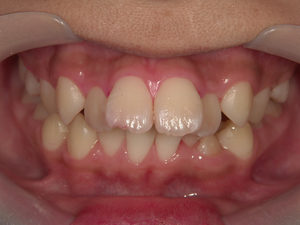

虫歯の治療、矯正の相談をご希望され来院されました。お口の中を診査(レントゲン写真、口腔内写真、視診)させていただいたところ、虫歯については問題なくきれいに歯磨きされているようでした。 正面から見るとジグザグしており、お口 […]

全体的な歯並びの矯正治療を行いました。治療期間は3年間。

ジグザグの歯並びを気にされてご来院されました。. 見た目の問題も大切ですが、それ以上に清掃がしにくいために虫歯・歯周病に非常になりやすく、不正咬合(良くないかみ合わせ)は顎の関節に負担をかけてしまい顎関節症を引き起こす可 […]

歯の大きさに対する顎の大きさのスペース不足により歯が並びきらず、ジグザグの歯並びおよび上の前歯が出っ歯になっていました。 左右4番の歯を抜歯することにより歯を並べるスペースを確保し、歯並びを揃えました。 全体の歯並びが綺 […]